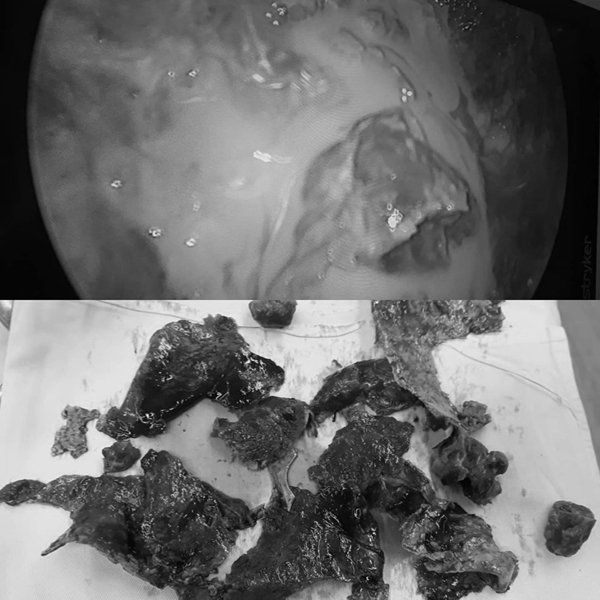

BS Hồ Thái Phúc, khoa Phẫu thuật Tim mạch lồng ngực, BV Hữu nghị đa khoa Nghệ An cho biết, khi mở ra, trong phổi bệnh nhân có rất nhiều mủ đặc và cặn mủ đã được phân cách bởi nhiều khoang.

| Hình ảnh mủ bao quanh phổi bệnh nhân và các cặn mủ keo cứng được lấy ra |

Bằng các động tác phẫu thuật cẩn thận, ekip đã bóc trọn vỏ của ổ cặn, nhờ đó phổi nở phục hồi nhanh chóng. Cuối cùng, bác sĩ đặt 2 ống dẫn lưu to, một ống tưới rửa để rửa màng phổi liên tục.